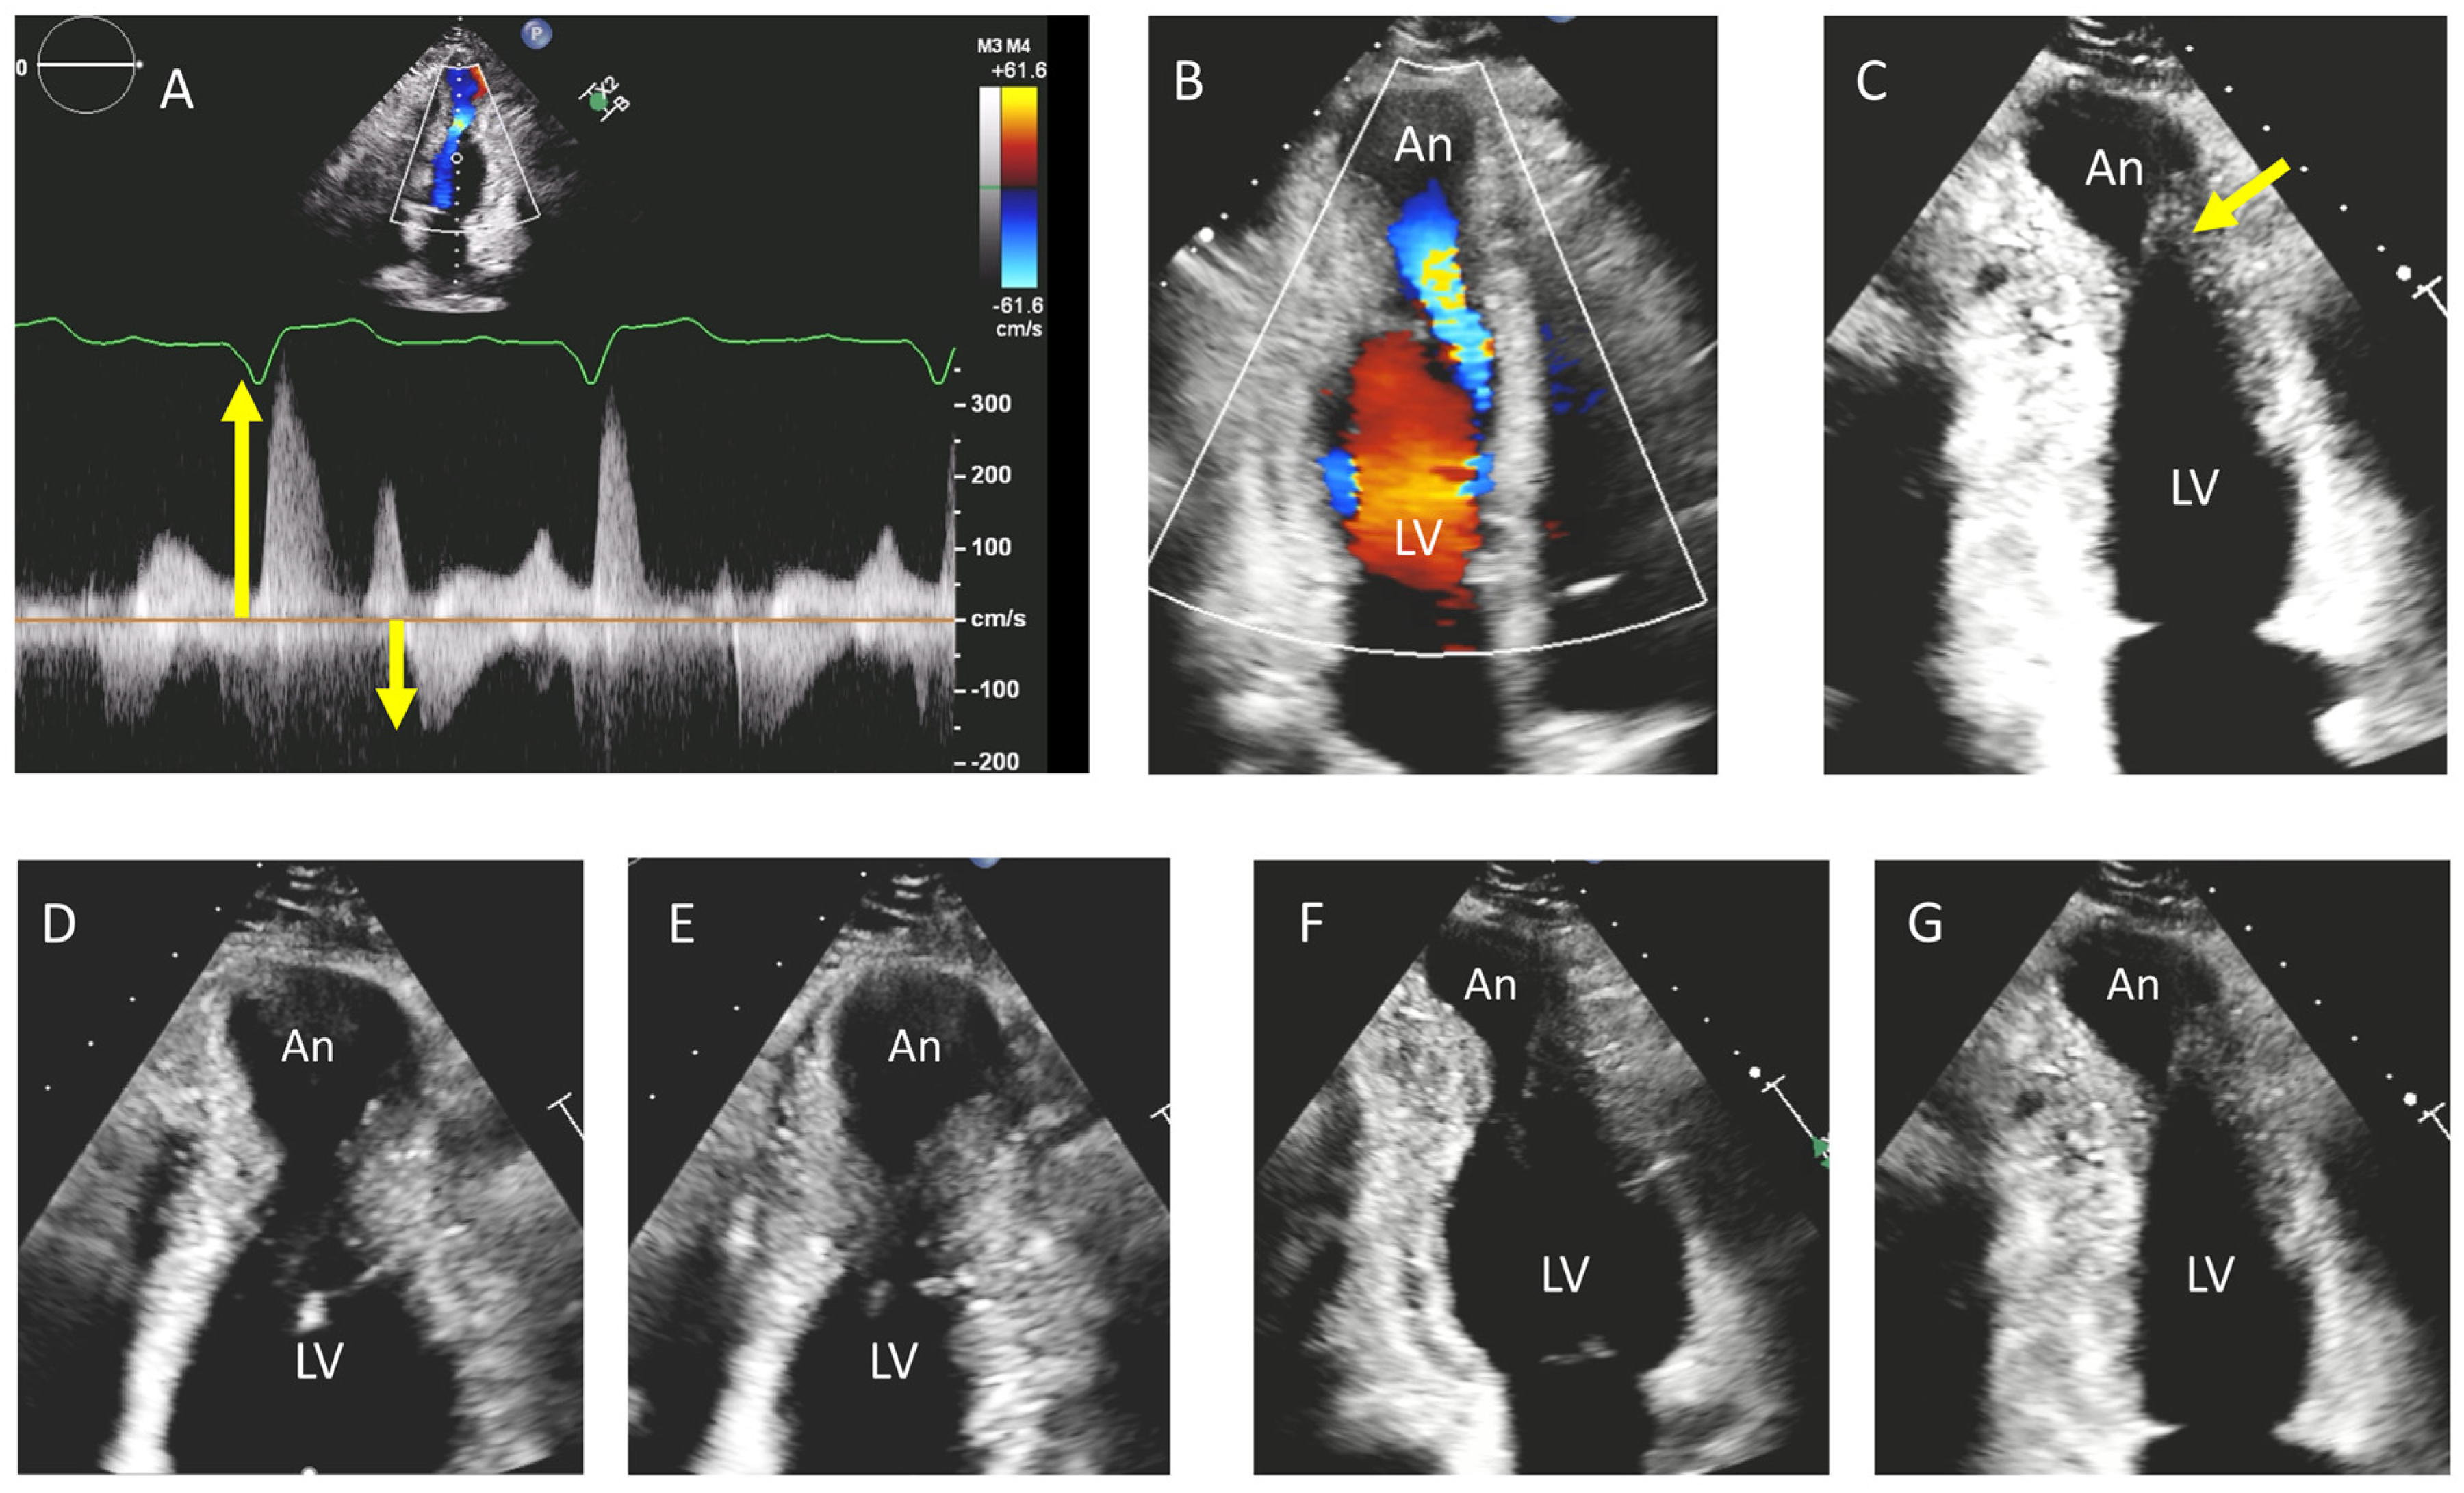

- Lo Russo, G.V.; Pepi, M.; Mushtaq, S.; Mantegazza, V.; Celeste, F. Is There a Typical Doppler Pattern in Patients With Apical Hypertrophic Cardiomyopathy With Aneurysm? JACC Case Rep. 2023, 14, 101836. [Google Scholar] [CrossRef]